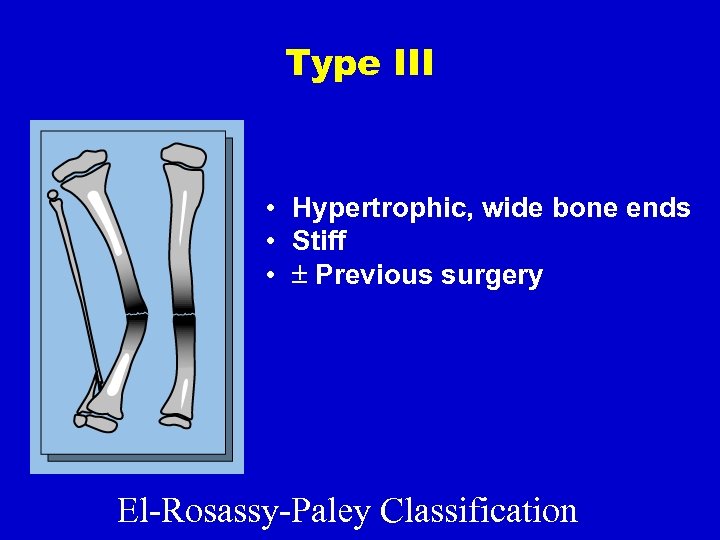

Type III • Hypertrophic, wide bone ends • Stiff • Previous surgery El-Rosassy-Paley Classification